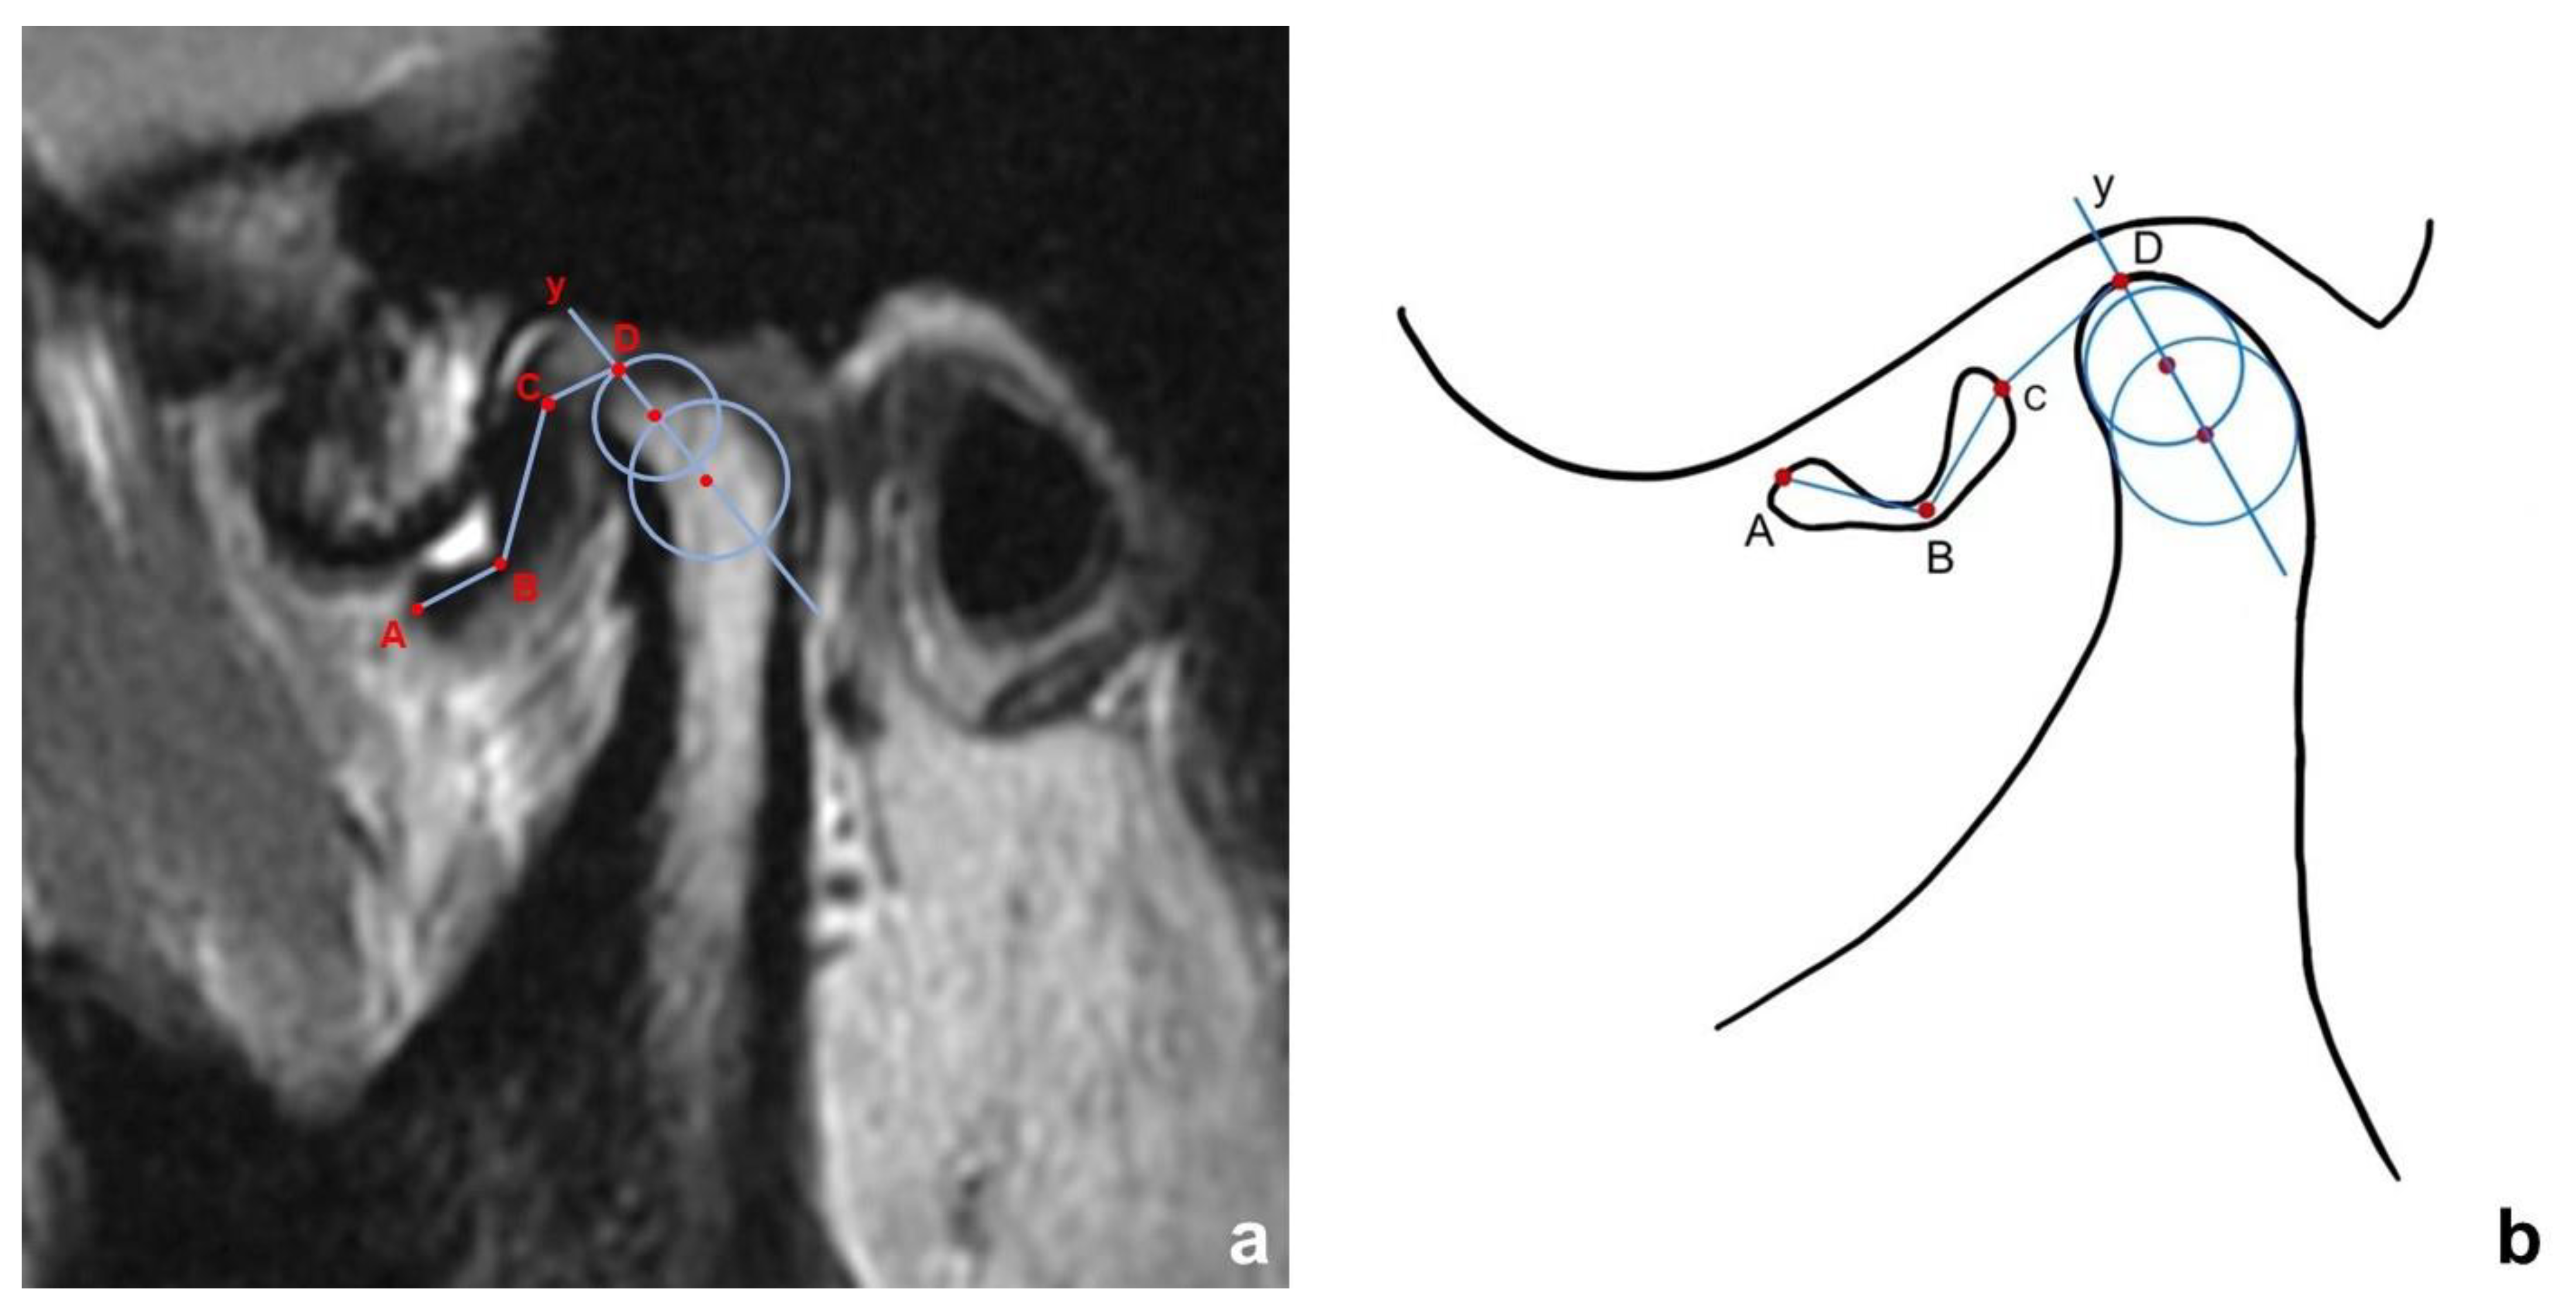

2.3.1. Determination of Disc Displacement

2.3.2. Quantitative Measurements of Disc Morphology

- Arayasantiparb, R.; Tsuchimochi, M. Quantification of disc displacement in internal derangement of the temporomandibular joint using magnetic resonance imaging. Odontology 2010, 98, 73–81. [Google Scholar] [CrossRef]

- Yang, Z.; Wang, M.; Ma, Y.; Lai, Q.; Tong, D.; Zhang, F.; Dong, L. Magnetic Resonance Imaging (MRI) Evaluation for Anterior Disc Displacement of the Temporomandibular Joint. Med. Sci. Monit. Int. Med. J. Exp. Clin. Res. 2017, 23, 712–718. [Google Scholar] [CrossRef]